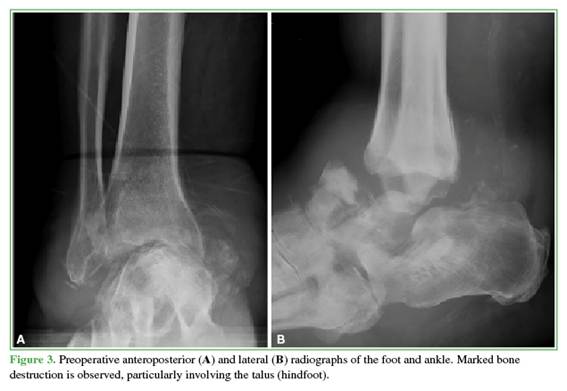

At the end of follow-up, seven patients had achieved stable healing of the TTC arthrodesis (Figures 3 and 4). Two developed fibrous healing, which allowed ambulation with orthotic support. One patient required a delayed revision and remains under follow-up. The median time to radiographic healing was 8.6 months (IQR 25-75%: 4.7–8.6).